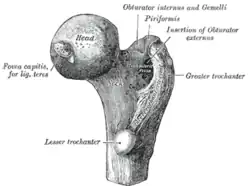

Oberschenkelknochen (Femur)

Der Oberschenkelknochen bildet am oberen Ende einen großen kugelförmigen Kopf (Caput femoris). Dieser stellt eine relativ regelmäßig gekrümmte Zwei-Drittel-Kugel mit einem Radius von durchschnittlich 2,5 Zentimetern dar. Lediglich der gelenknahe (proximale) Pol formt eine plane Fläche um die Einziehung des Oberschenkelknochenkopfes (Fovea capitis femoris), um die zu übertragende Last von einem Punkt auf einen Ring zu verschieben. Der Oberschenkelknochenkopf ist durchgehend von hyalinem Knorpel überzogen, weist in seinen Hauptbelastungszonen jedoch eine besonders ausgeprägte Schicht von etwa 2,5 bis 3,5 Millimetern auf. Zum Oberschenkelknochenhals (Collum femoris) hin nimmt die Dicke sukzessiv ab.

Auswärtsdreher

Die tiefe hintere Schicht der hinteren, äußeren Hüftmuskulatur wird auch als „kleine Beckengesellschaft“ bezeichnet. Sie besteht aus den beiden Hüftlochmuskeln (Musculus obturator internus und Musculus obturator externus), den beiden Zwillingsmuskeln (Musculus gemellus superior und Musculus gemellus inferior) und dem viereckigen Oberschenkelmuskel (Musculus quadratus femoris). Alle Muskeln bewirken eine Auswärtsdrehung, ebenso der Birnenmuskel (Musculus piriformis).